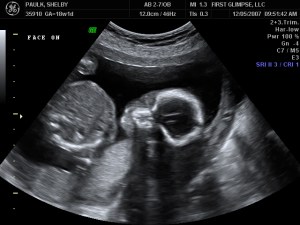

We had the ultrasound for baby number #2 on Tuesday, as we like to refer to HIM as (at least until we come up with a name, which could be a while given our track record). Yes, I said HIM…we are having a baby BOY!! We are so blessed to be have one of each. God is so good. Here are a few of the many ultrasound pictures that were taken. God has blessed us with one very healthy baby and we pray that this little guy is just as healthy. So far the docs. say everything looks great, we’ll have another ultrasound around 28 weeks because of where the placenta is located right now. It needs to move because it is blocking the cervix, but the ultrasound tech said that 9 of 1o times it will move…we pray that it does, because if it doesn’t I will have to have a C-Section.